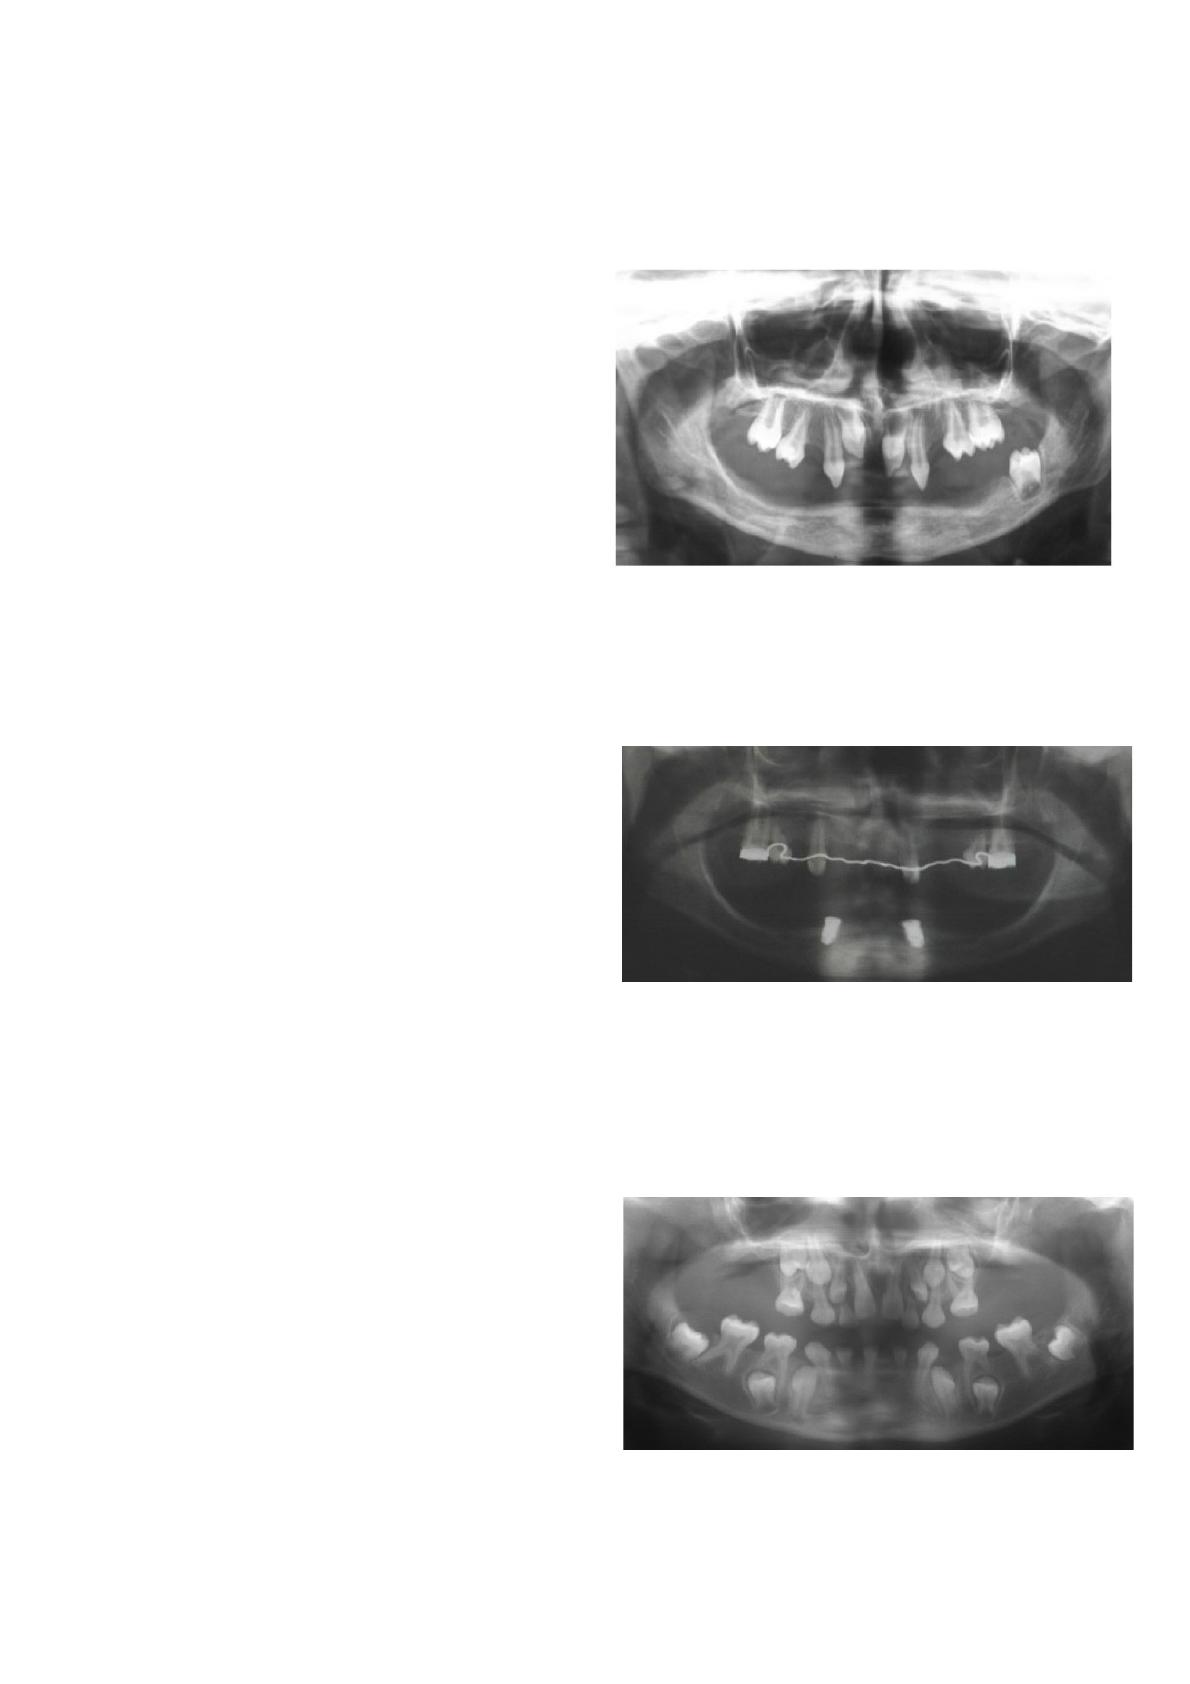

coll., 2013 ; Bergendal et coll., 2015) (Fig 1 : tableau

radiologique d’une oligodontie sévère associée à une dysplasie

ectodermique liée à l’X chez un patient âgé de 7 ans, Centre de

Référence pour les Manifestations Bucco-dentaires des

Maladies Rares de Strasbourg). Plus de 25 ans de suivi

bons résultats prothétiques et une absence de complications

implantaires majeures (Fig 2: implants symphysaires

ostéointégrés chez un patient âgé de 10 ans présentant une

dysplasie ectodermique autosomique, Centre de férence

pour les Manifestations Bucco-dentaires des Maladies Rares de

Strasbourg).

homéotique PAX9 (Fig 3 : tableau radiologique associé à une

oligodontie isolée chez un patient âgé de 7 ans, Centre de

Maladies Rares de Strasbourg). Dans ce dernier cas de figure,

Fig 1 : tableau radiologique d’une oligodontie sévère

associée à une dysplasie ectodermique liée à l’X chez un

patient âgé de 7 ans (Centre de Référence pour les

Manifestations Buccodentaires des Maladies Rares de

Fig 2 : implants symphysaires ostéointégrés chez un

patient âgé de 10 ans présentant une dysplasie

ectodermique autosomique (Centre de Référence pour les

Fig 3 : tableau radiologique associé à une oligodontie

isolée chez un patient âgé de 7 ans (Centre de Référence

pour les Manifestations Bucco-dentaires des Maladies

Rares de Strasbourg).